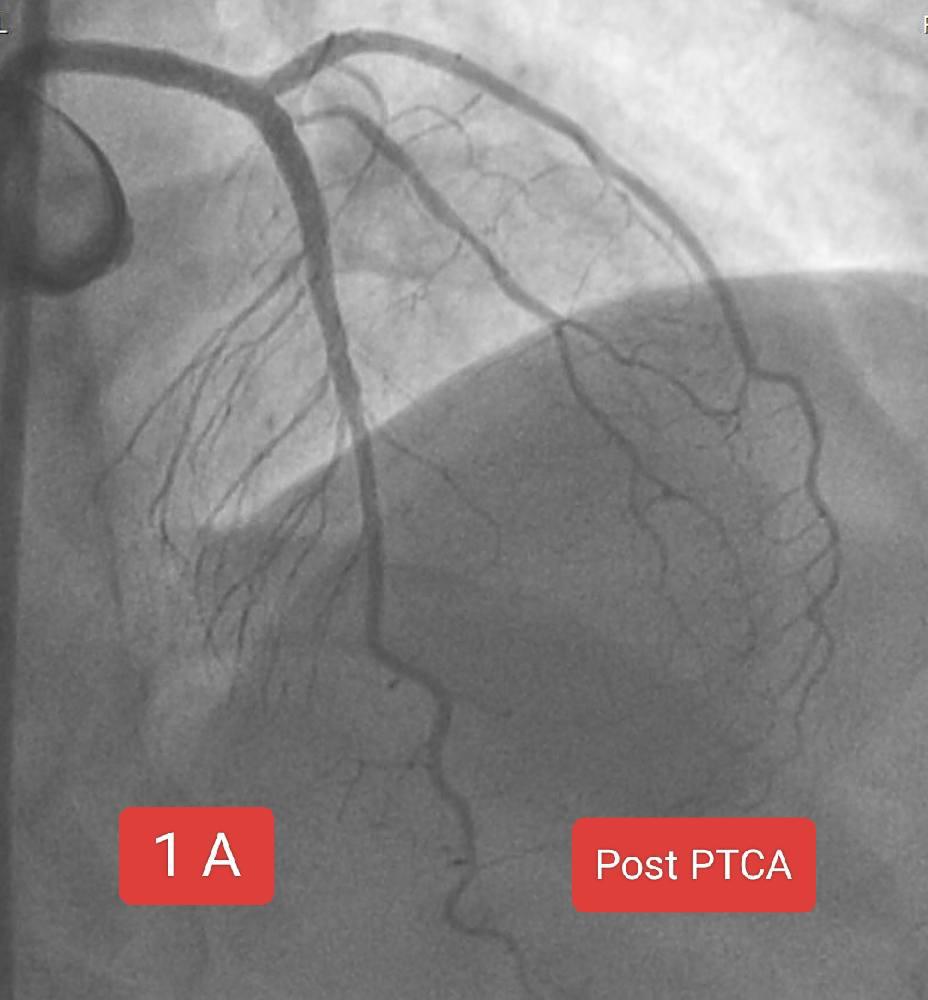

60 year old male patient presented with acute onset chest pain since 2 hours. ECG SHOWED inferior wall STEMI ECHO showed No RWMA , Normal LV SYSTOLIC function The timing of intervention is absolutely critical when performing Primary PTCA for a patient with STEMI. This is because heart muscle (myocardium) begins to die within minutes after a coronary artery is occlude. The longer the delay, the more myocardial tissue is irreversibly damaged. The ideal goal is a door to balloon time 90 minutes (from hospital arrival to inflation of the balloon). Each 30-minute delay increases 1-year mortality by up to 7.5%. In this case we successfully managed to shift the patient to lab with 15 minutes of arrival. Angiogram showed 100% thrombotic cut off in mid RCA. Wiring and successful thrombosuction was followed by prompt stenting all within 15 minutes of arrival to cath lab.